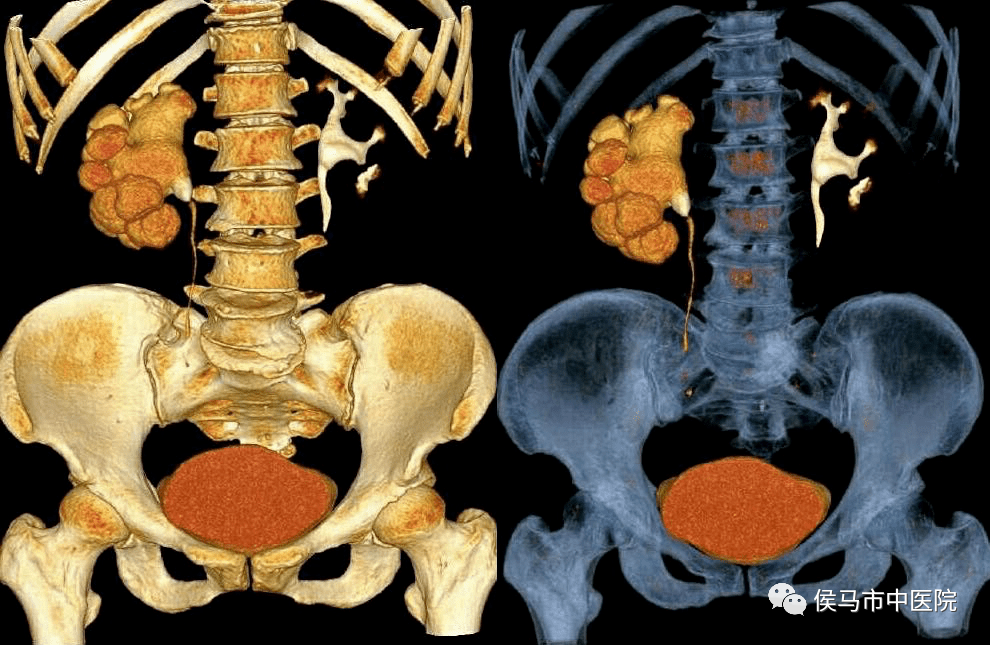

6、泌尿系CT造影(CTU)

CTU能够清晰显示泌尿系病变位置、大小、范围、与周围组织间的关系,能准确定位及定性,为尿路结石、肿瘤等多种疾病提供直观清晰的影像信息,集合了传统CT、B超及静脉肾盂造影(包括逆行尿路造影)的优点。